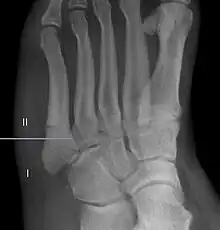

For several reasons, a Jones fracture may not unite. The diaphyseal bone (zone II), where the fracture occurs, is an area of potentially poor blood supply, existing in a watershed area between two blood supplies,[14] this may compromise healing. In addition, there are various tendons, including the peroneus brevis and fibularis tertius; these may pull the fracture apart and prevent healing.[24]

Zones I has been associated with relatively guaranteed union and this union has taken place with only limited restriction of activity combined with early immobilization. On the other hand, zone II has been associated with either delayed or non-union and, consequently, it has been generally agreed that fractures in this area should be considered for some form of internal immobilization, such as internal screw fixation.[25]

These zones can be identified anatomically and on x-ray adding to the clinical usefulness of this classification.[26] Surgical intervention is not, by itself, a guarantee of cure and has its own complication rate. Other reviews of the literature have concluded that conservative, non-operative, treatment is an acceptable option for the non-athlete.[27]

-

Anatomy of the fifth metatarsal. -

2 zone description